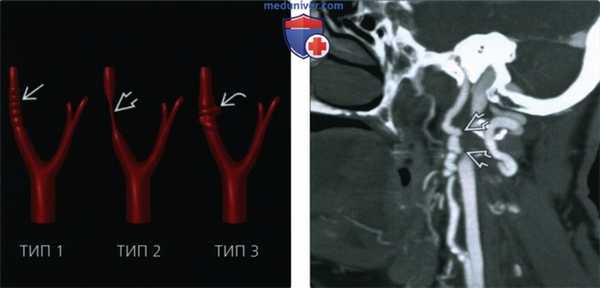

(Слева) Схема бифуркации общей сонной артерии, показаны основные варианты фиброзно-мышечной дисплазии. Тип 1 -чередующиеся участки сужения и расширения сосуда S3; тип 2 - протяженный участок стеноза; тип 3-участки неровности с формированием дивертикула.

(Справа) КТ-ангиография, реконструкция в сагиттальной проекции. Деформация внутренней сонной артерии по типу «четок». При более детальном рассмотрении обеих артерий также удалось обнаружить участки выпячивания сосудов, которые характерны для дисплазии 3 типа.

2. КТ при фиброзно-мышечной дисплазии сонной артерии:

• КТ-ангиография:

о Характерные изменения обнаруживаются в сонных и позвоночных артериях:

- Изгибы/неровность контуров артерий в виде «четок»

- Стеноз артерии без отложения в ее стенке кальция (ср. с дефектом предресердно-желудочковой перегородки)

- Может сочетаться с расслоением артерии, псевдоаневризмой, внутричерепными аневризмами

• Цифровая субтракционная ангиография (DSA): золотой стандарт диагностики, 3 варианта:

о Тип 1 (85%): признак «четок», медиальная фиброплазия

о Тип 2 (10%): протяженный участок стеноза, фиброплазия интимы

о Тип 3 (5%): асимметричное выбухание с одной стороны артерии; периадвентициальная фиброплазия